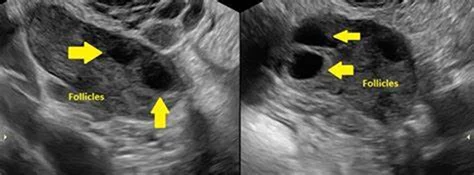

متلازمة تكيس المبايض هي حالة صحية تتسم بتضخم المبايض ووجود مجموعات صغيرة من الكيسات المملوءة بالسائل. تؤثر هذه الحالة بشكل كبير على توازن الهرمونات لدى المرأة. عادةً ما يمكن للنساء اللاتي تتراوح أعمارهن بين 15 و44 عامًا أن يعانين من هذه المشكلة الصحية. تشخيص دقيق ضروري لتلقي العلاج المناسب. تؤكد أخصائية النساء لدينا على أهمية الفحص للكشف المبكر والوقاية.